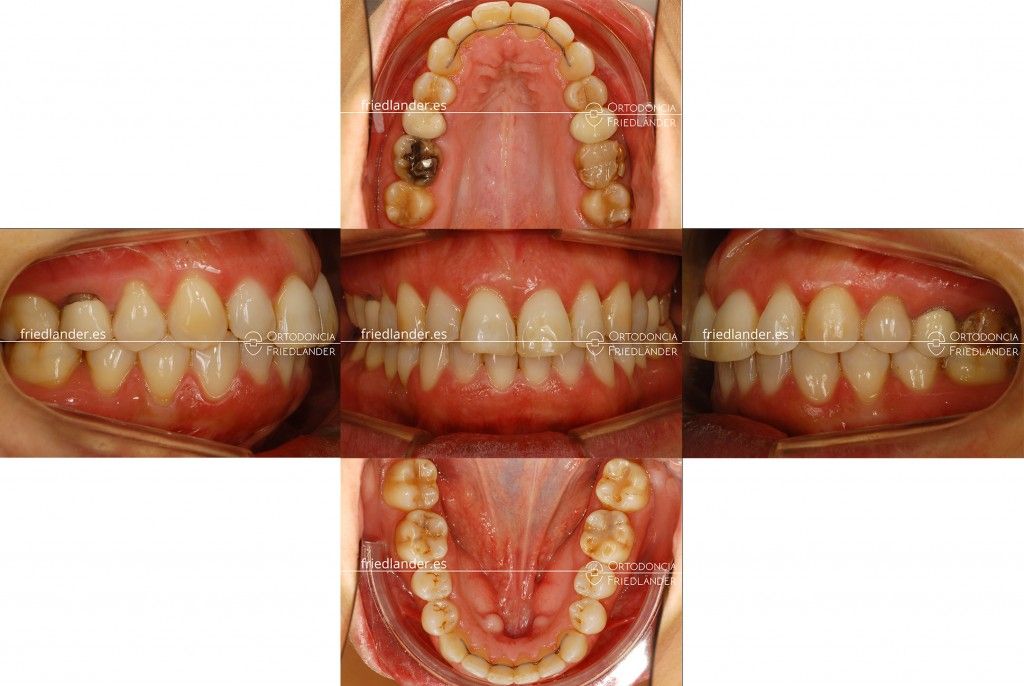

Resultados

A los 22 meses de tratamiento conseguimos una buena clase I y cerrar del todo la mordida abierta anterior.

La paciente está muy contenta con los resultados de la ortodoncia y ahora esta pediente de cambiar alguna corona y hacer una pequeña fase estética.